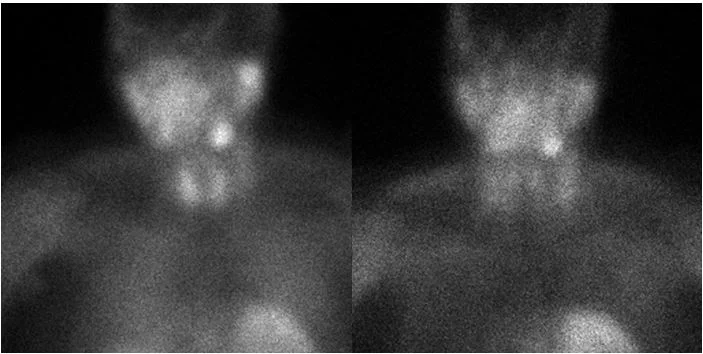

Early and delayed sestamibi scan images are unremarkable. Uptake in left lower neck is in the submandibular gland.